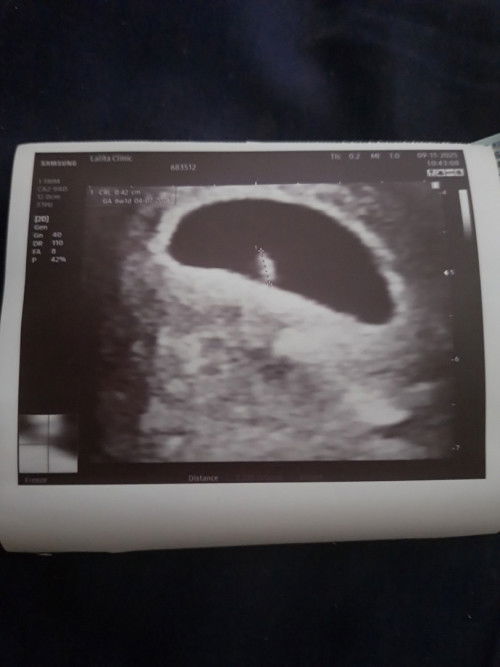

แม่ๆแต่ละบ้านซาวด์เจอน้องกันตอนกี่วีคคะ บ้านนี้ไปซาวด์ตอน 6 วีค ไม่เจอถุงตั้งครรภ์กับตัวน้องเลยค่ะ คุณหมอให้ไปซาวด์อีกทีเดือนหน้า แต่คุณหมอบอกว่าอาจจะเป็นเพราะมดลูกต่ำหรือมีภาวะแท้งคุกคาม มีแม่ๆบ้านไหนเป็นเหมือนกันหรือคล้ายๆกันบ้างไหมคะ🙇🏻‍♀️#ขอบคณสำหรับคำตอบล่วงหน้านะคะ

เจอน้องตอน6วีคค่ะ ซาวด์ผ่านหน้าท้อง

Post reply image